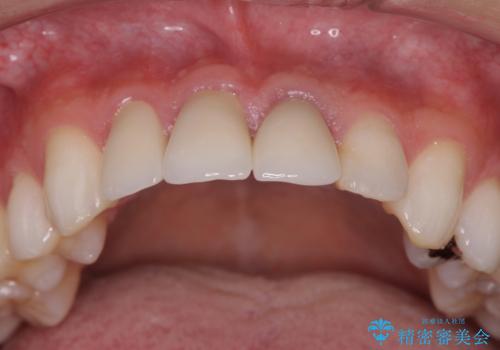

- 前歯の変色や形態を含む、見た目を改善したいと希望され来院されました。

・歯の変色 →ジルコニアクラウンの製作